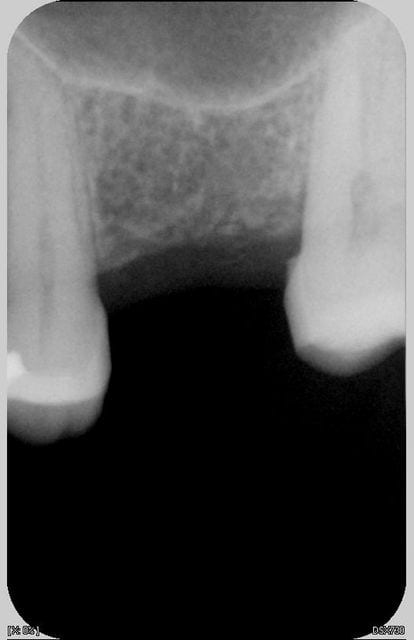

c'est la 2ème fois que fais une élévation de sinus par voie alvéolaire. La technique est rapide et non invasive et surtout simple (pour un débutant comme moi). Le petit dôme radio-opaque à l'apex de l'implant fait plaisir à voir.

7mm de hauteur d'os disponible

Implant 10mm x 5 (Seven de M.I.S)

un p'tit Summers du samedi matin: sur le cliché post op on distingue le fragment de corticale qui a sauté avec le premier ostéotome.

(implant tekka progress 4.5 13, os autogène récupéré lors du forage)